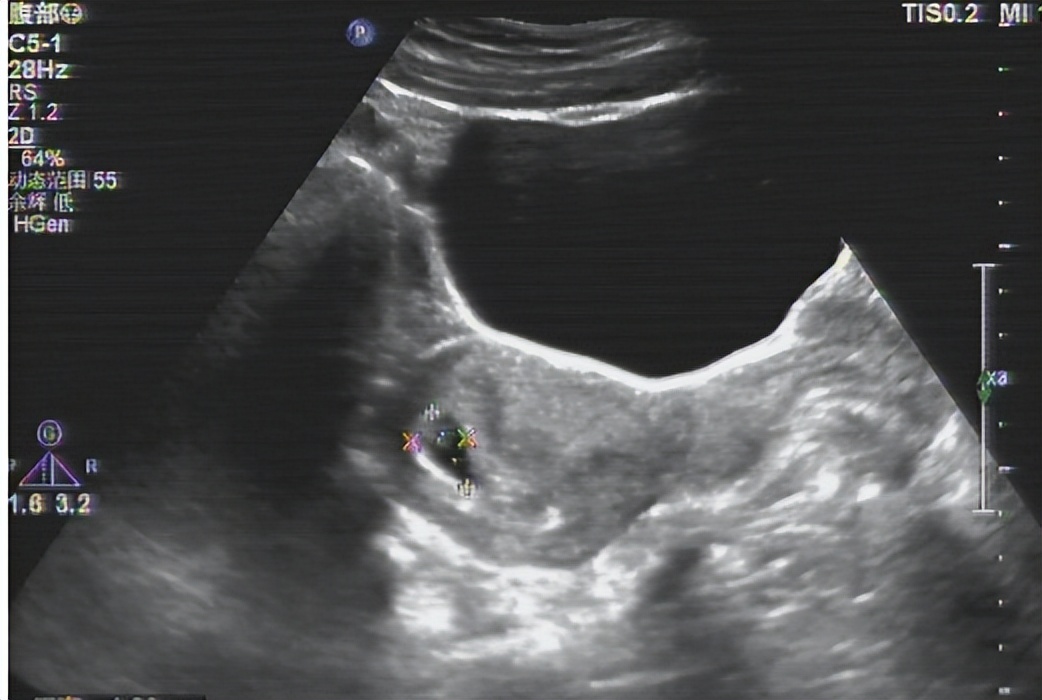

所以你到医院看不孕的时候, 妇科医生一般会让你先做一个B超排除子宫有没有存在畸形的这种可能。

并且优生优育项目中会给女性做一个子宫以及附件的B超,这样可以较早的了解自己身体的初始情况。